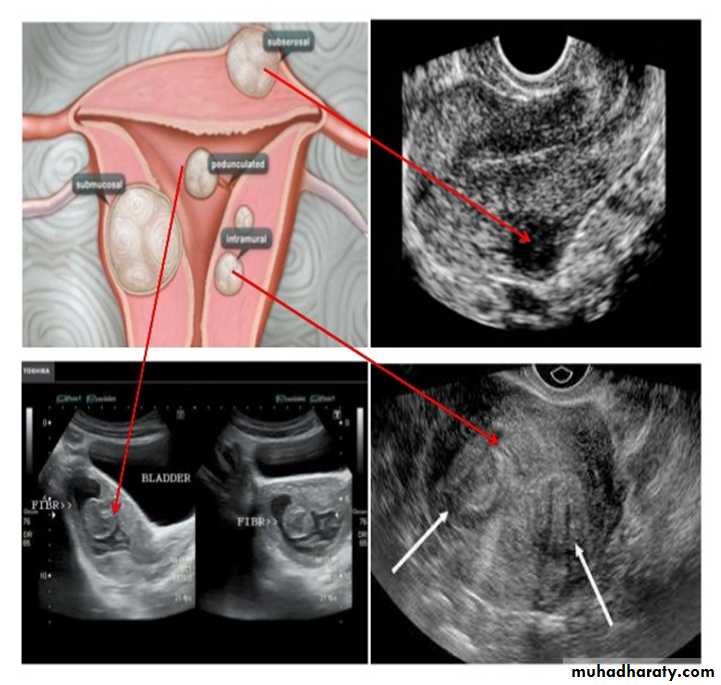

UUUUUUs of pelvic organs

Uterine fibroid

Ovarian cysts